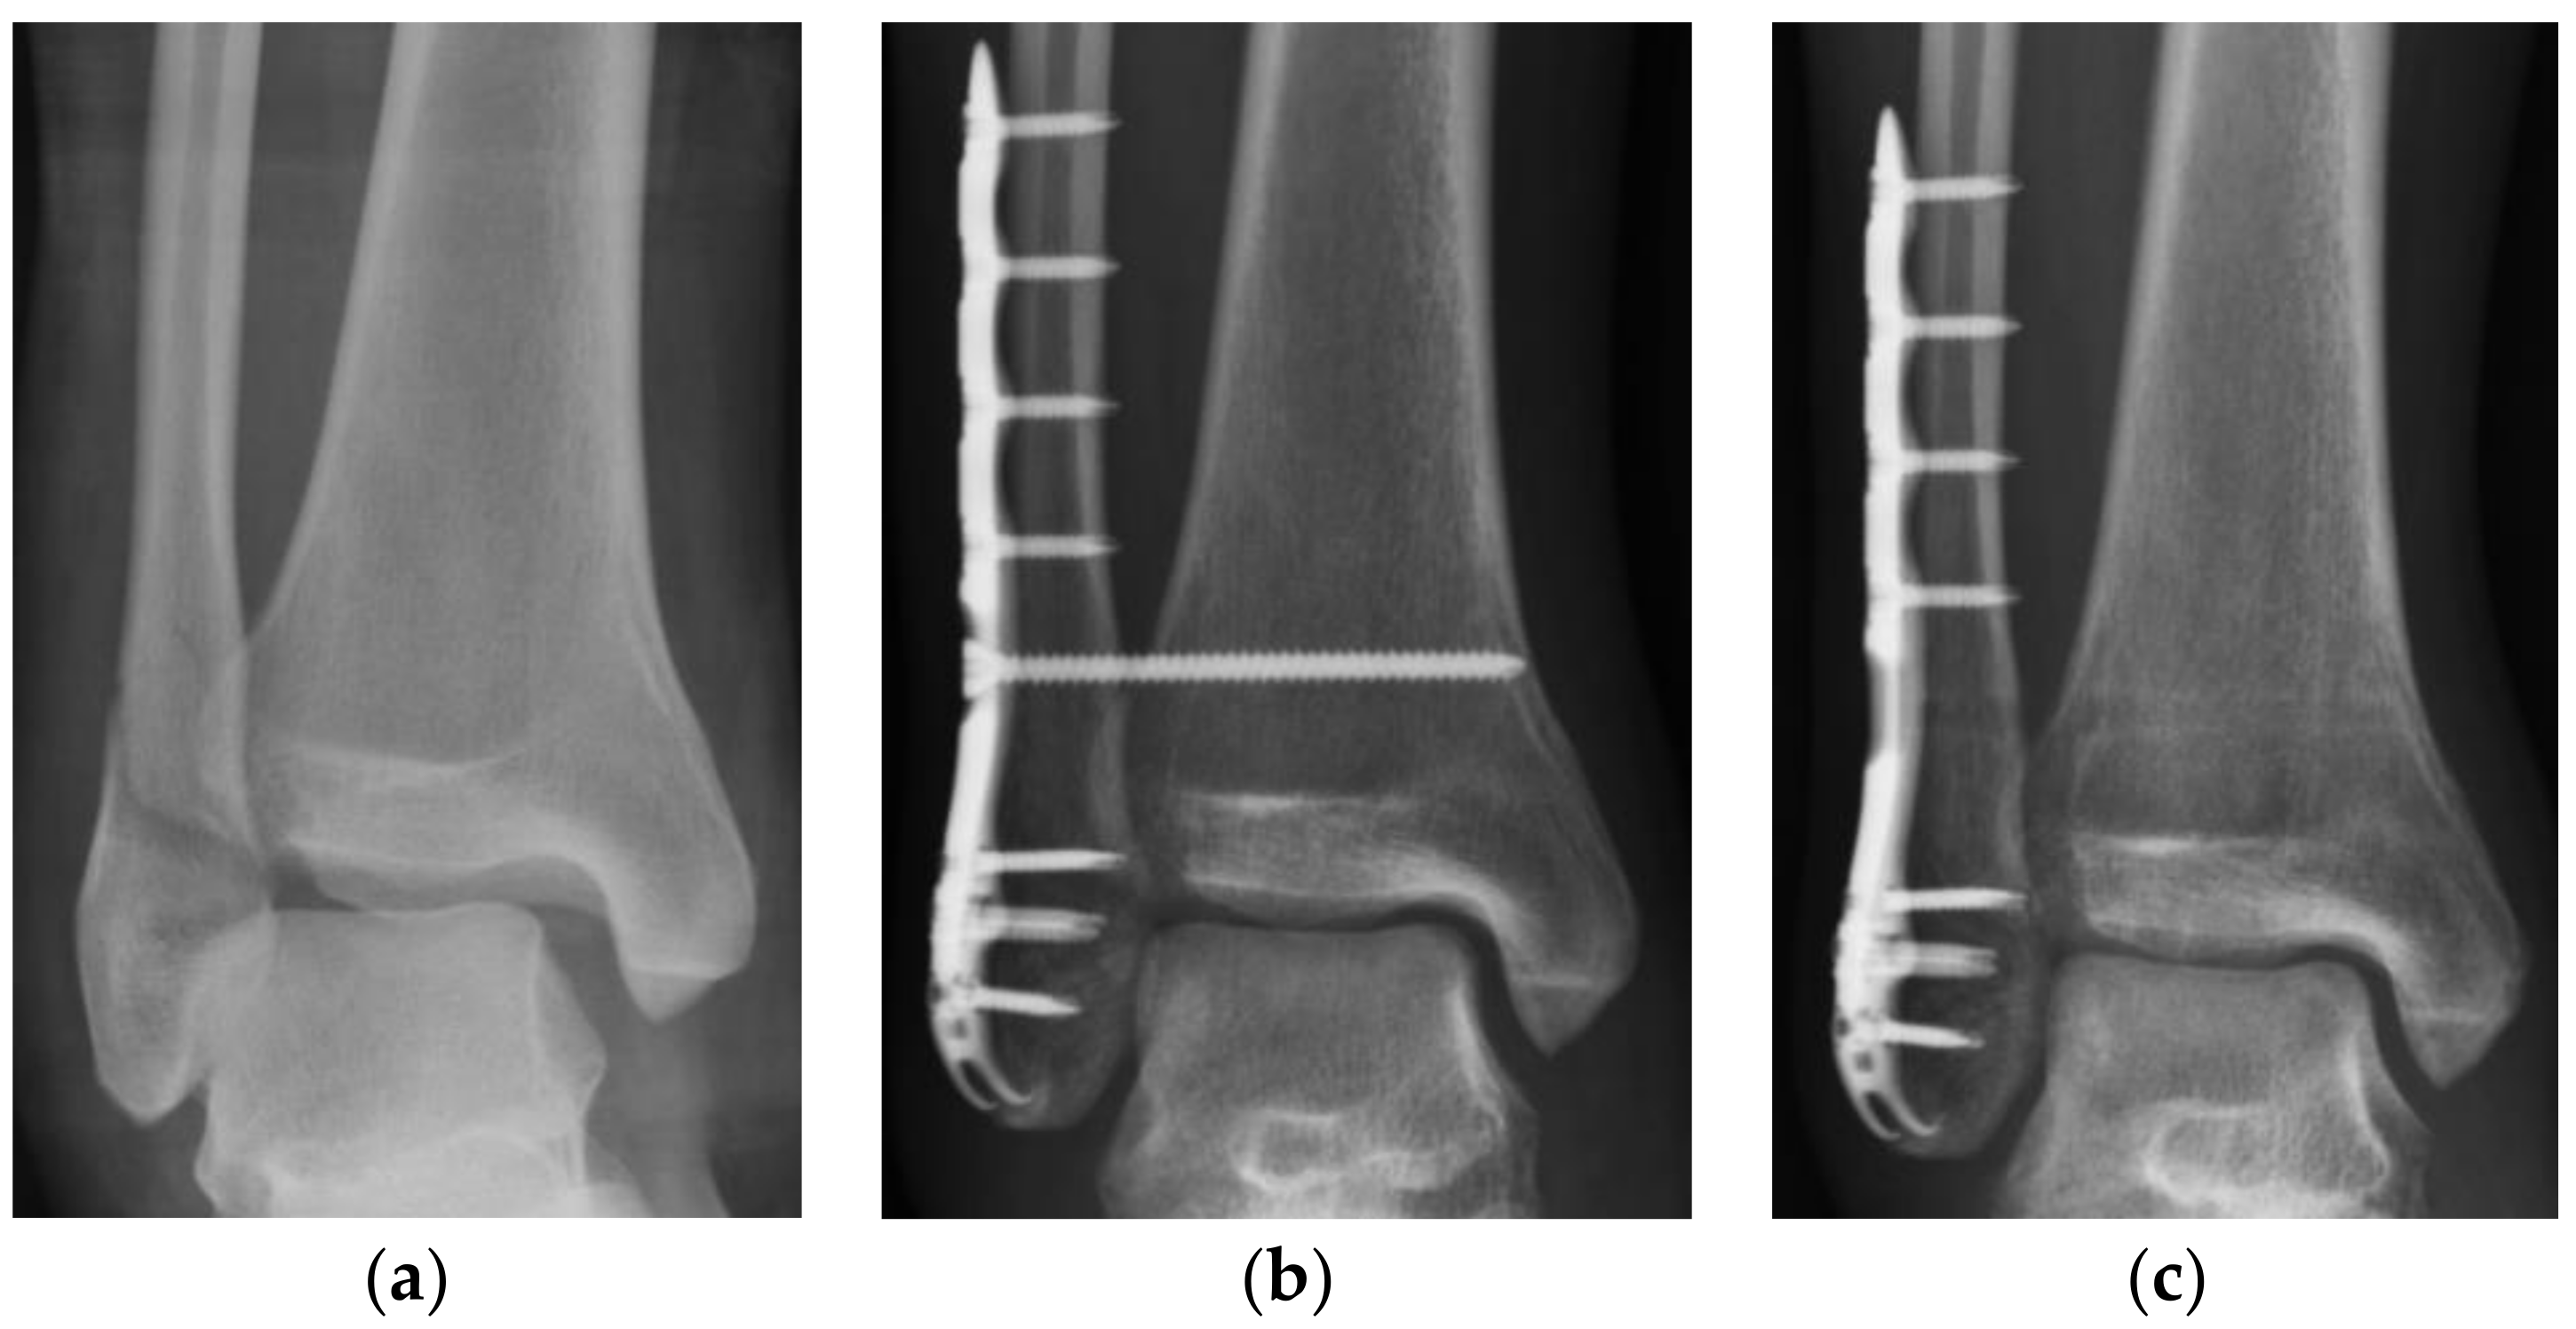

For each standard ankle anteroposterior (AP) radiograph, tibiofibular overlap (OL), tibiofibular clear space (CS), and medial clear space (MCS) were measured. The OL was defined as the distance between the lateral border of the anterior tibial prominence and the medial fibula 1 cm proximal to the tibial plafond [8]. The CS was defined as the distance between the lateral border of the posterior tibial malleolus and the medial aspect of the fibula measured 1 cm proximal to the tibial plafond [8]. The MCS was defined as the distance from the lateral border of the medial malleolus to the medial border of the talus at the level of the talar dome (Figure 1) [8]. A radiolucent zone is always found between the implant and the surrounding bone, usually parallel to the implant surface. In our study, we defined the positive radiolucent line as a radiolucent zone more than half of the syndesmosis screw.

Figure 1. Radiographic evaluation in the study. The tibiofibular clear space (CS) was defined as the distance between the lateral border of the posterior tibial malleolus and the medial aspect of the fibula, measured 1 cm proximal to the tibial plafond. The medial clear space (MCS) was defined as the distance from the lateral border of the medial malleolus to the medial border of the talus at the level of the talar dome. The tibiofibular overlap (OL) was measured from the lateral border of the anterior tibial prominence to the medial fibula 1 cm proximal to the tibial plafond.